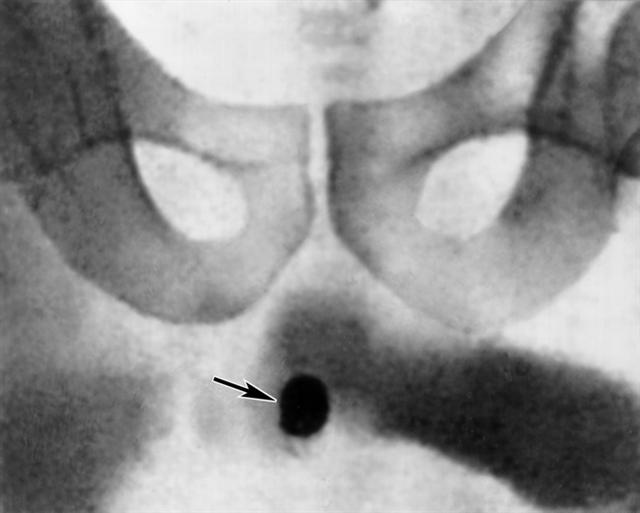

Рис. 2. Обзорная рентгенограмма лобковой области больного с камнем в мочеиспускательном канале (тень камня указана стрелкой).